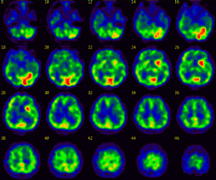

治療後の脳血流画像

治療後に再度検査を行うと、治療前に青色だった部分が緑色に変わって表示されており、血流が回復したことがわかります。